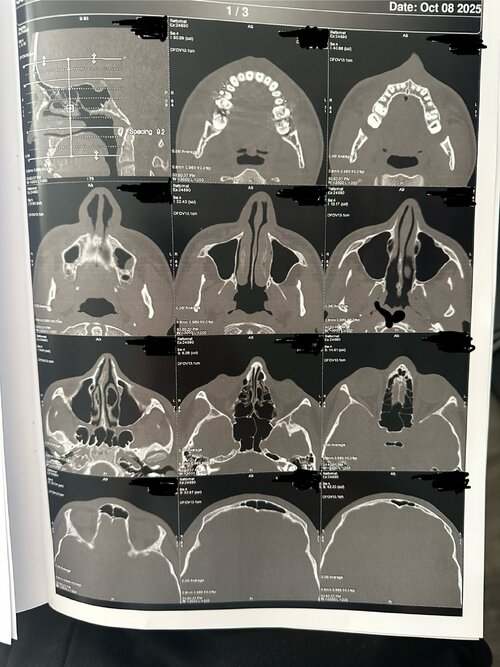

I did a facial ct scan and i’m gonna show what chat gpt said about my scan because it’s hard to understand it by just looking.

The CT scan provides a detailed view of the upper airway, nasal passages, and palate from multiple angles (axial, coronal, and sagittal). Based on the visible structures, several key anatomical features can be observed that relate to breathing efficiency, oral posture, and orthodontic development.

1. Palate Shape and Width

The palate appears relatively narrow and high-arched, forming more of a V-shaped rather than a broad U-shaped curve. This configuration suggests transverse constriction of the upper jaw (maxilla), particularly in the posterior region behind the first molars. A deeper palatal vault like this often corresponds to reduced nasal floor width and limited tongue space, which can influence breathing patterns and oral posture.

The midpalatal suture, which is the joint dividing the left and right halves of the maxilla, appears visible but may be partially fused due to age. At 16 years old, this suture is typically less responsive to traditional expansion methods, though it may still show some flexibility depending on individual skeletal development.

Overall, the palate’s form and proportions suggest a mild to moderate skeletal constriction, which could influence both dental crowding and airway size.

2. Nasal Airway

The nasal passages appear structurally clear, with no major obstruction or sinus blockage. The nasal septum seems mostly straight, though there may be a minor deviation toward one side in the lower portion. The inferior turbinates (soft tissue ridges inside the nasal cavity) show slight asymmetry, which is common and can contribute to uneven airflow between sides.

Because the palate forms the floor of the nasal cavity, a narrow palate typically reduces nasal base width. This can result in less efficient airflow through the nose, encouraging mouth breathing or snoring, especially during sleep. Expansion of the palate — if possible — can indirectly increase nasal volume, improving airflow and breathing comfort.

3. Airway and Oral Space

The sagittal (side) views reveal a moderately sized airway, with no extreme constriction but signs of limited space behind the soft palate and tongue. The soft palate extends close to the back wall of the throat (posterior pharynx), which may slightly narrow the oropharyngeal space. The tongue appears positioned relatively low, likely adapting to the narrow, high-arched palate, which offers limited lateral room for rest posture.

Together, these features suggest an airway that is functional but not maximally open, meaning airflow could be mildly restricted, particularly during sleep or nasal congestion.

The CT scan provides a detailed view of the upper airway, nasal passages, and palate from multiple angles (axial, coronal, and sagittal). Based on the visible structures, several key anatomical features can be observed that relate to breathing efficiency, oral posture, and orthodontic development.

1. Palate Shape and Width

The palate appears relatively narrow and high-arched, forming more of a V-shaped rather than a broad U-shaped curve. This configuration suggests transverse constriction of the upper jaw (maxilla), particularly in the posterior region behind the first molars. A deeper palatal vault like this often corresponds to reduced nasal floor width and limited tongue space, which can influence breathing patterns and oral posture.

The midpalatal suture, which is the joint dividing the left and right halves of the maxilla, appears visible but may be partially fused due to age. At 16 years old, this suture is typically less responsive to traditional expansion methods, though it may still show some flexibility depending on individual skeletal development.

Overall, the palate’s form and proportions suggest a mild to moderate skeletal constriction, which could influence both dental crowding and airway size.

2. Nasal Airway

The nasal passages appear structurally clear, with no major obstruction or sinus blockage. The nasal septum seems mostly straight, though there may be a minor deviation toward one side in the lower portion. The inferior turbinates (soft tissue ridges inside the nasal cavity) show slight asymmetry, which is common and can contribute to uneven airflow between sides.

Because the palate forms the floor of the nasal cavity, a narrow palate typically reduces nasal base width. This can result in less efficient airflow through the nose, encouraging mouth breathing or snoring, especially during sleep. Expansion of the palate — if possible — can indirectly increase nasal volume, improving airflow and breathing comfort.

3. Airway and Oral Space

The sagittal (side) views reveal a moderately sized airway, with no extreme constriction but signs of limited space behind the soft palate and tongue. The soft palate extends close to the back wall of the throat (posterior pharynx), which may slightly narrow the oropharyngeal space. The tongue appears positioned relatively low, likely adapting to the narrow, high-arched palate, which offers limited lateral room for rest posture.

Together, these features suggest an airway that is functional but not maximally open, meaning airflow could be mildly restricted, particularly during sleep or nasal congestion.